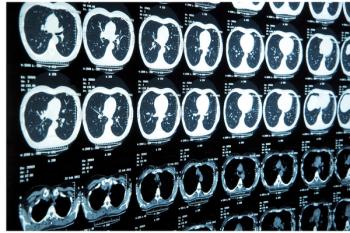

Computer-aided diagnosis was evaluated to determine efficacy in radiologic assessment of lung cancer.